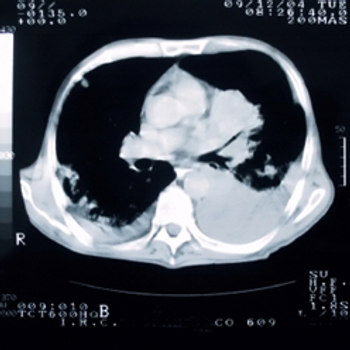

A 76-year-old man is found to have a right upper lobe mass. After further evaluation, a biopsy is performed. What is your diagnosis?